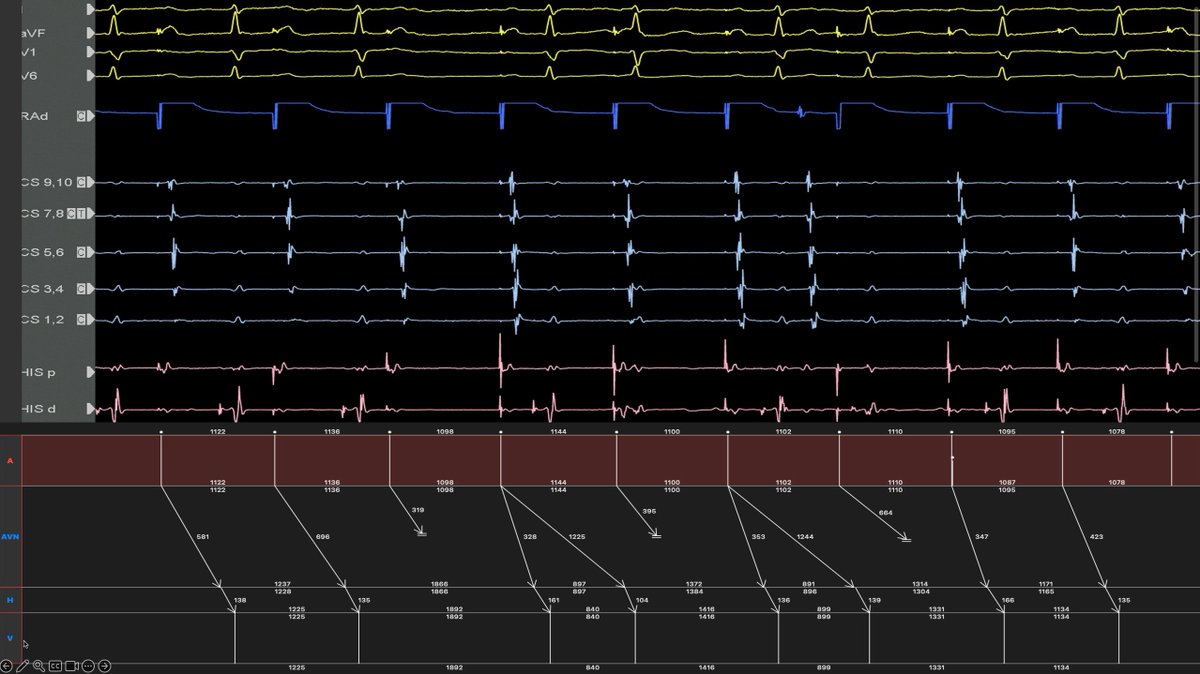

8/ End with a nice ladder diagram of the intracardiacs which allow me to see the His. I think it might be possible to construct other ladder diagrams consistent with the EGMs but this is what I came up with.

5/ So as @finnakerstrom suspected, we also thought this guy had DAVNNT - dual AV nodal non-reentrant tachy. Wildly different PR intervals, the QRS complexes identical to sinus but with one P to 2QRS is very suggestive. Here's a proposed ladder diagram of one of the ECGs. #EPeeps